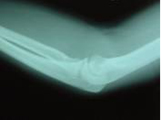

X線所見:上の写真では橈骨頸部の骨折が認められ、やや傾斜した状態の転移が認められました。また橈骨頭部に2ヶ所の骨折が認められました。こちらは、大きな転移は認められませんでした。

この写真は、整復後の写真です。傾斜した転移は十分に正常位置に整復されていることが確認されています。この写真は、8週目(58日目)のレントゲン写真です。骨折部位は治癒と判断されました。